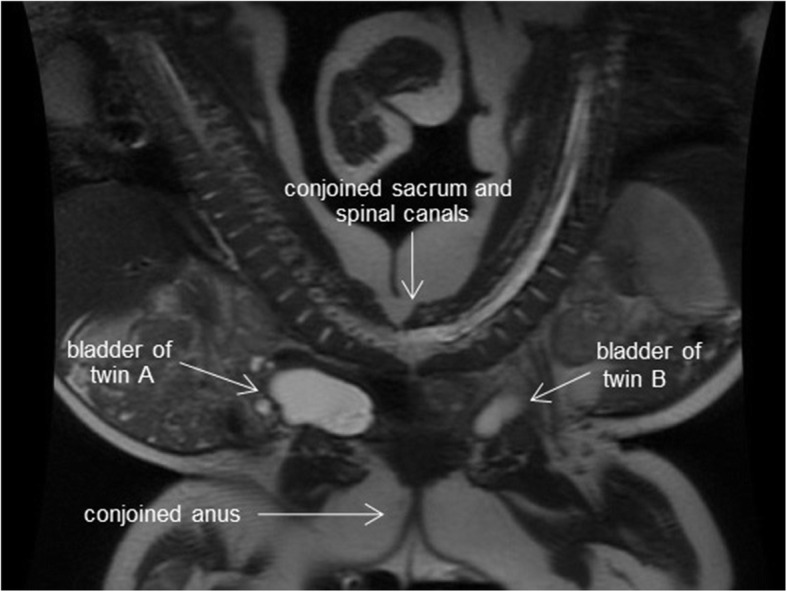

Suspected pygopagus conjoined twin boys (prenatal diagnosis) were born by elective cesarean section at 35 weeks gestation. Their total birth weight was 4.69 kg; they did not require resuscitation, and their Apgar scores at 1 and 5 min after birth were 8 and 9, respectively, in both twins. Magnetic resonance imaging revealed that they were conjoined from the sacrum to the perineum, sharing the sacrum, coccyx, anus, and urethra (Fig. 1). Neither baby had any other apparent abnormalities. Their growth after birth was satisfactory, and the separation surgery was scheduled at 5 months. The total weight of the twins at the time of surgery was 13.8 kg, with both twins being approximately the same size. Conjoined twins share major/minor blood vessels, resulting in varying degrees of cross-circulation. The imaging results suggested that cross-circulation was limited in this case.

Fig. 1.

Magnetic resonance imaging of the pygopagus twins; they shared the sacrum, coccyx, anus, and urethra. Each had a separate bladder